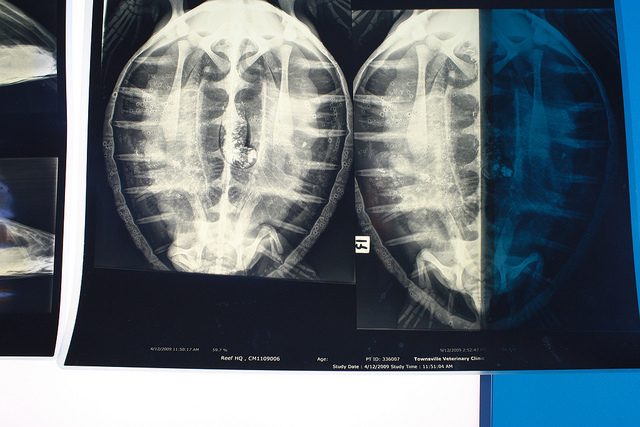

Rentgen želve. Foto: Mads Boedker, Flickr CC